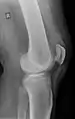

Quadriceps tendon rupture in plain X-ray

X-ray of a tear of the patellar tendon. On the left: The kneecap is pulled up. On the right: Significant dent in the soft tissue above the kneecap.